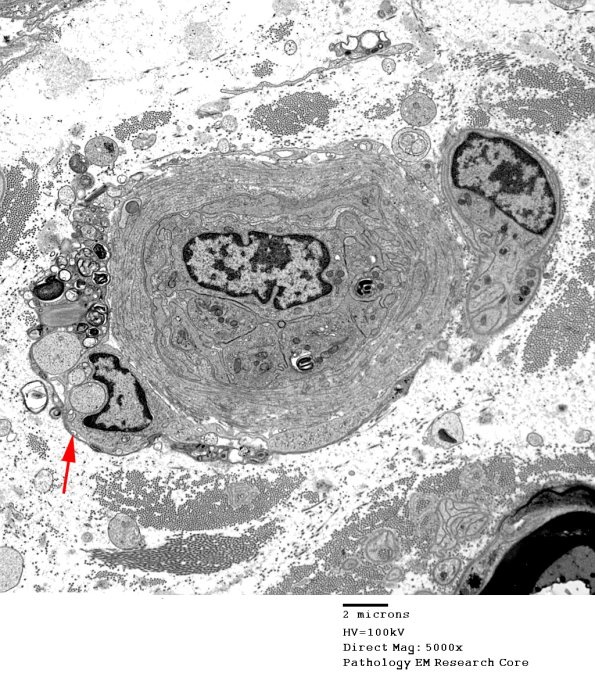

Once myelin has been phagocytosed by macrophages they accumulate adjacent to the endoneurial microvasculature. (electron micrograph)